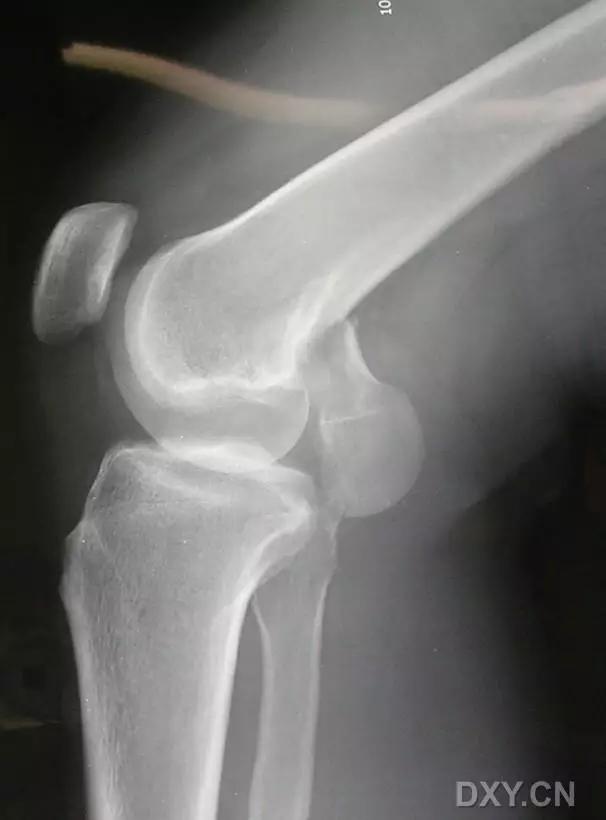

5. Hoffa 骨折

指股骨远端冠状面的骨折。

病例 1:一般股骨髁间、髁上粉碎骨折中含 Hoffa 骨折的不少见,但单纯后髁骨折则很少见。

正位片

侧位片